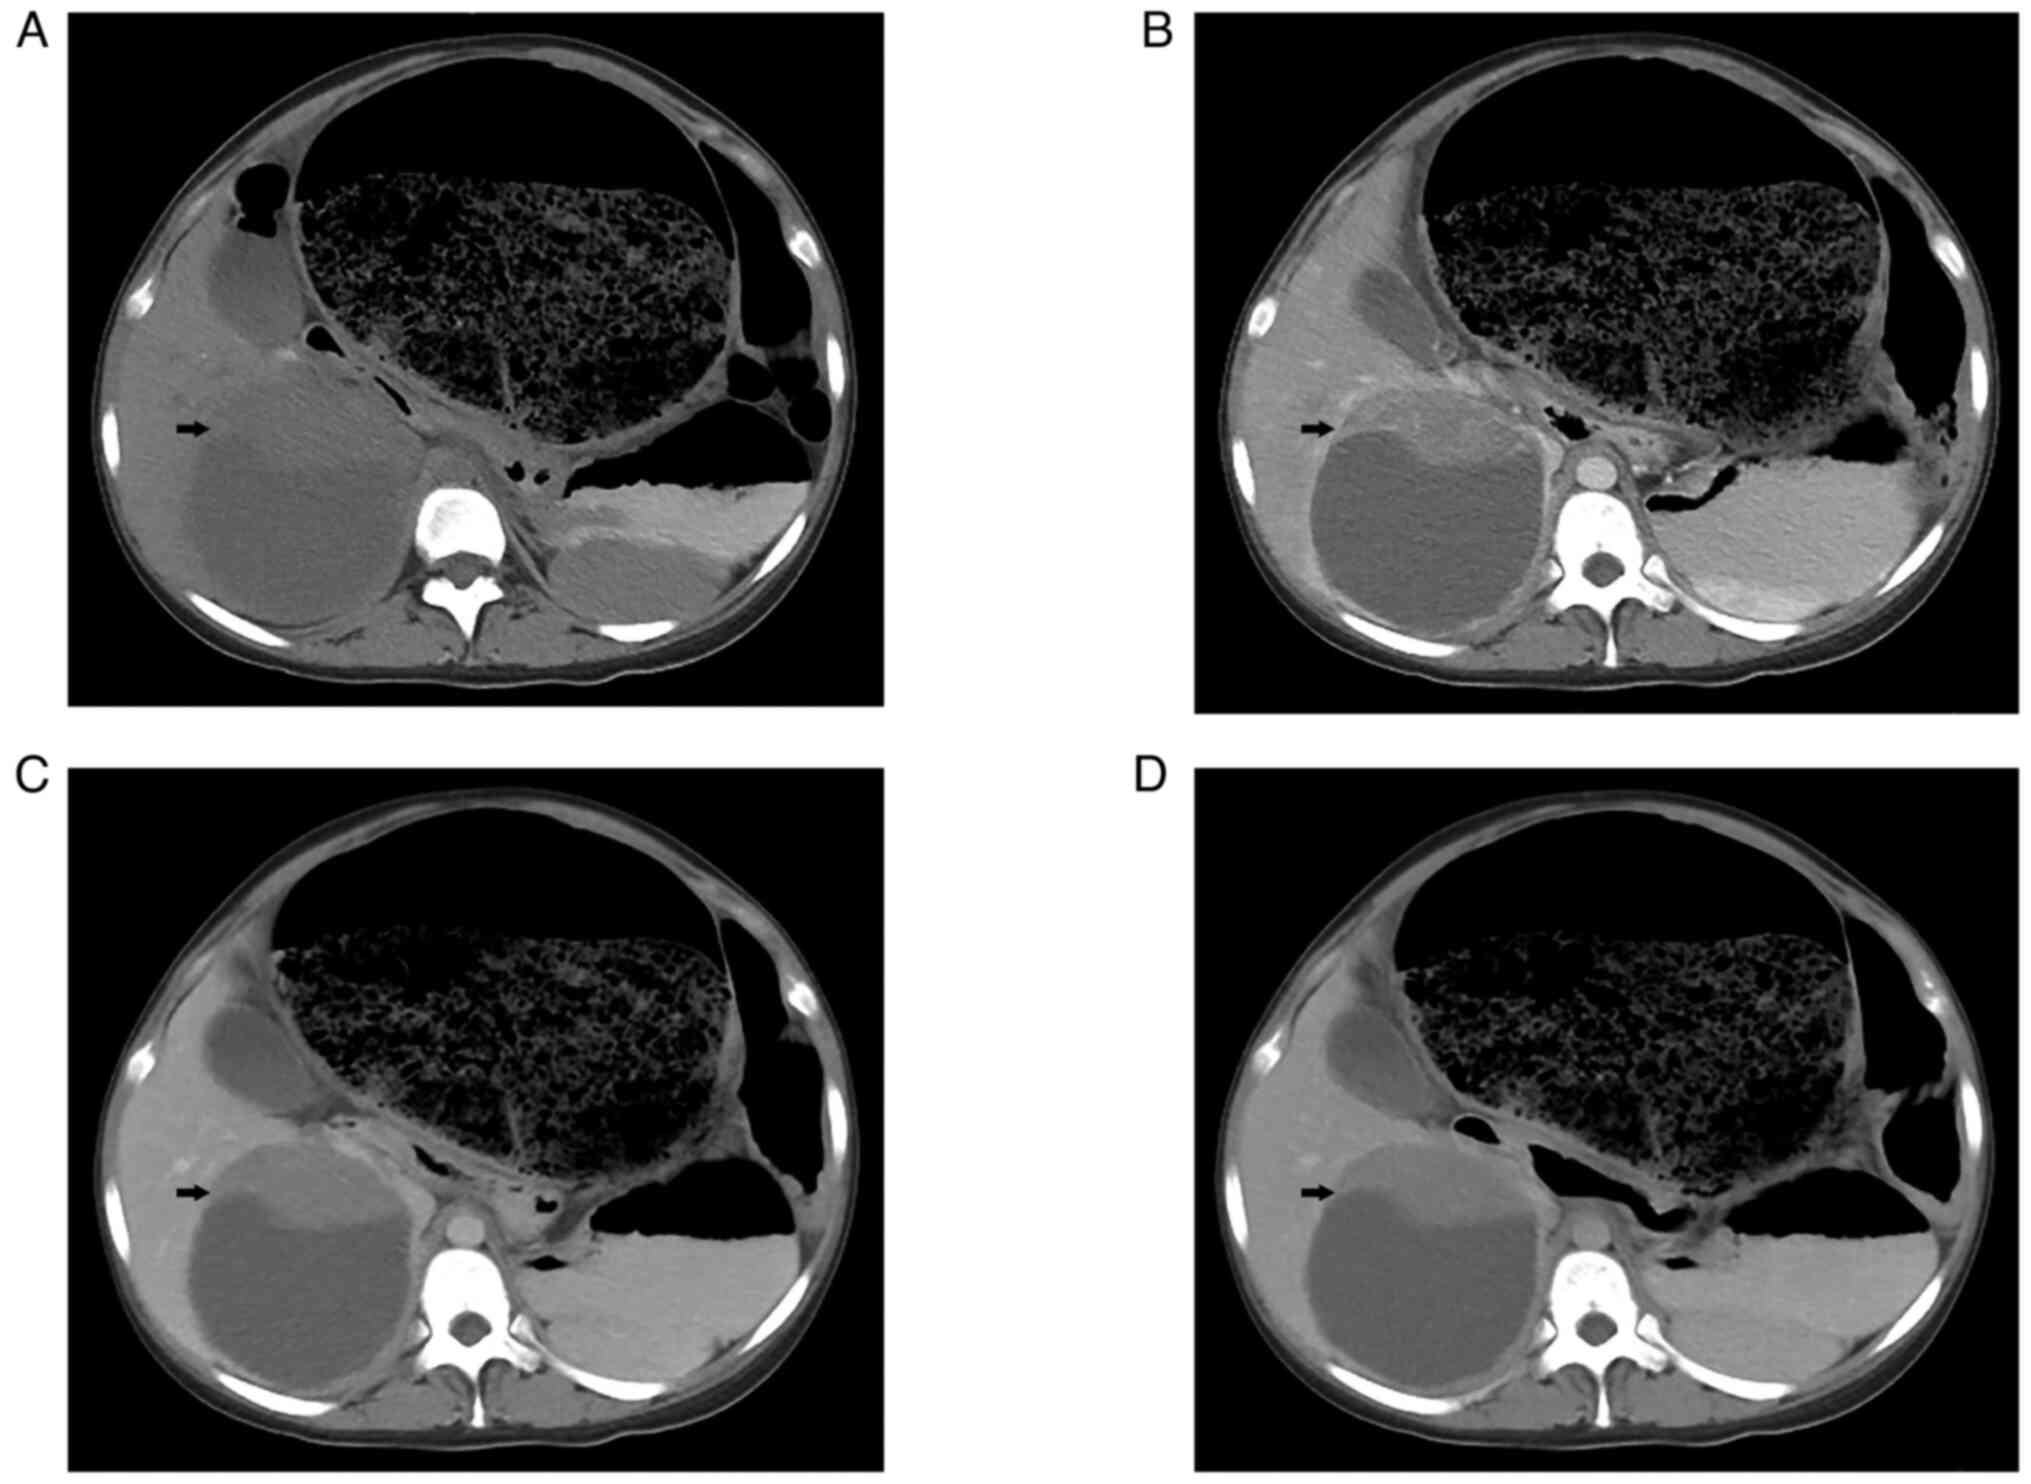

Following admission, ultrasound examination showed a solid-cystic mass with a size of 11.4×10.2 cm in the right lobe of the liver, which was considered benign disease. A CT scan of the entire abdomen showed a large, round, hypodense mass with a solid and well-marginated periphery. A contrast-enhanced CT scan revealed that the solid portion of the abdominal circumference displayed strong enhancement in the arterial phase. In addition, several tortuous blood vessels were observed (Fig. 1). The sigmoid colon and rectum were obviously distended and expanded, filled with gas and intestinal contents. The maximum diameter of the colon was 20 cm. The patient did not undergo MRI examination. In addition, gastrointestinal angiography and colonoscopy were not performed due to intestinal contents. Finally, the patient was diagnosed with iron-deficiency anemia, liver damage and megacolon.

Figure 1.

Preoperative abdominal and contrast-enhanced CT images. (A) Abdominal CT scan revealed a large, round and hypodense mass with a solid and well marginated periphery (arrow). (B) Abdominal contrast-enhanced CT images revealed that the solid portion displayed intense enhancement in the arterial phase (arrow). Enhancement was also observed (arrow) at the (C) portal and (D) delayed phases. The sigmoid colon and rectum were well distended and expanded and filled with gas and intestinal contents.